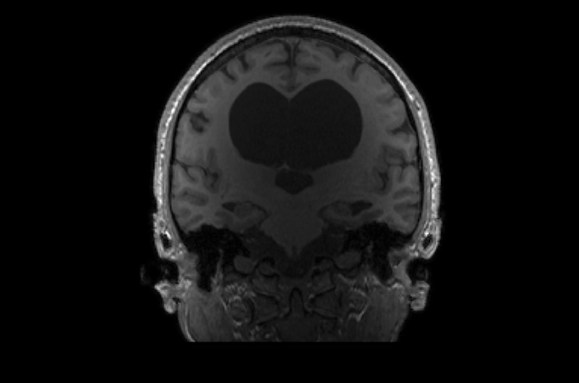

As of May 30, the Interesting Brains Project had scanned the brains of 30 people. Some have holes in their frontal or temporal lobes; others are missing parts of their cerebellum, a brain structure involved in balance and movement. Still other participants have brain matter that’s squished up against the sides of their skull; scans show voids that appear to have ballooned from the brain’s center.

Hydrocephalus has left its mark in K.V.’s brain, pushing neural tissue toward the sides of their skull and pressing the cortex thin. K.V.’s ventricles, cavities filled with cerebrospinal fluid (center), are larger than most people’s and form a fluid-filled void in the center of the brain. K.V. makes their living as a writer. COURTESY OF THE FEDORENKO LAB -